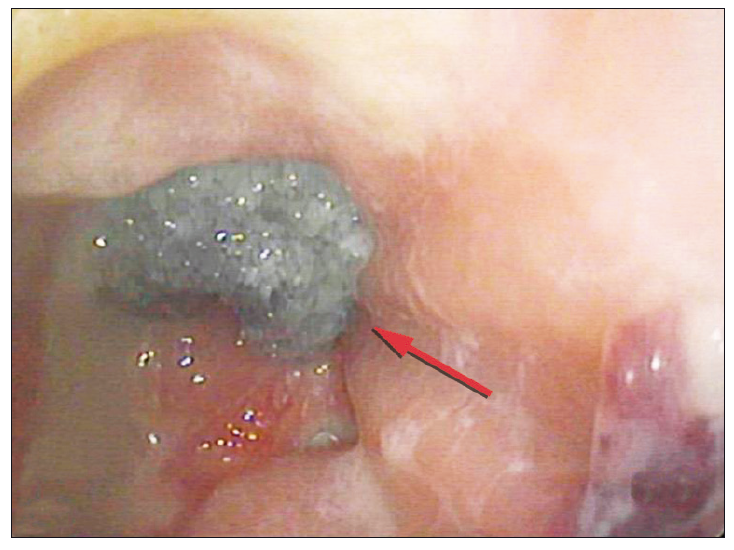

Figura 2. Videorectosigmoidoscopia: cavidad de la dehiscencia (flecha

amarilla)

Se presenta el caso de una mujer de 76 años con antecedentes de obesidad y un adenocarcinoma de recto (T2N1M0) por el que se realizó neoadyuvancia con quimioradioterapia (4500cGy) y posteriormente resección anterior del recto por una remisión incompleta, con colorrecto anastomosis baja (6 cm del margen anal) y confección de ileostomía de protección. Luego del alta, al decimoquinto día postoperatorio la paciente refirió dolor abdominal y salida de secreción purulenta y fétida por el ano, por lo que se decidió volver a internarla. En el laboratorio se observó la presencia de anemia normocítica-normocrómica (Hb 10,3 g/dl), sin leucocitosis, plaquetas de 287.000 10^3/uL, tiempo de protrombina de 100%, INR 0,99, con valores de velocidad de eritrosedimentación y proteína C reactiva normales. En la TAC de abdomen y pelvis se observó un aumento de la densidad de la grasa mesentérica a nivel de la región del flanco izquierdo y adyacente al colon descendente, huellas quirúrgicas y, a nivel rectal, una imagen con nivel hidroaéreo contigua a la anastomosis (Figura 1A). La videorectosigmoidoscopía confirmó la presencia de una anastomosis permeable con una dehiscencia del 50% de la circunferencia y una longitud en su eje mayor de 80 mm (Figura 2). Se consideraron diferentes posibilidades terapéuticas, incluyendo el desmantelamiento de la anastomosis, el drenaje transanal con tubo anastomótico, el drenaje percutáneo y los procedimientos endoscópicos avanzados como la colocación de stents, clips o la terapia endoluminal asistida por vacío. Priorizando la preservación de la anastomosis, dado que la paciente no presentaba peritonitis, sepsis o falla multiorgánica, se optó por un tratamiento mínimamente invasivo tipo VAC, tras evaluar los costos, riesgos, beneficios y comorbilidades de la paciente. Por vía endoscópica, se colocó en la cavidad posterior a la dehiscencia un catéter con una esponja de poliuretano en su extremo, conectado a sistema de aspiración negativa continua a 150 mm Hg (Figura 3). Se realizaron sesiones de lavado y de recambio del drenaje y esponja cada 72 horas, requiriendo 3 recambios hasta obtener la obliteración de la cavidad con tejido de granulación. Al realizar el control tomográfico se observó la obliteración de la cavidad presacra, la esponja colocada y el catéter de succión (Figura 1B). Luego de ese último recambio se retiró de manera definitiva el sistema VAC (Figura 4). La paciente presentó una adecuada recuperación y se le otorgó el alta hospitalaria a las 48 horas de haber retirado el sistema VAC. A los tres meses se realizó un control endoscópico en el que se observó la permeabilidad de la anastomosis y la resolución completa de la dehiscencia (Figura 5) y a posteriori se realizó el cierre de la ileostomía de protección.